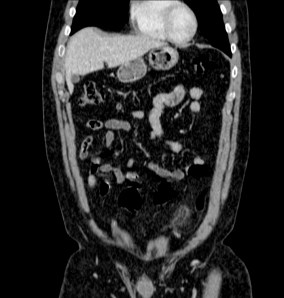

Se sospecha diverticulitis, se realiza TAC de abdomen:

Al igual que el caso anterior, nos encontramos nuevamente ante una apendagitis. Esta vez la sospecha era por diverticulitis, la anterior creíamos enfrentarnos a una apendicitis probablemente.

TAC: Imagen oval con aumento de la atenuación central, inferior a 5 cm de diámetro, contigüa al colon, con afectación de la grasa periférica. El aumento de la atenuación central es un signo de trombosis venosa muy útil para el diagnóstico, pero su ausencia no excluye en diagnóstico de apendagitis. Otros hallazgos, como aumento de la pared colónica o formación de abscesos son raros. Aunque los síntomas remiten en dos semanas, los cambios en la TAC pueden prolongarse más tiempo (pueden mantenerse, disminuir o quedar una atenuación residual), aunque en 6 mese suele haber remitido completamente. En Ecografía suele observarse en el área de máxima sensibilidad al dolor, una masa hiperecogénica, inferior a 5 cm, no compresible, adyacente al colon y sin señal Doppler.